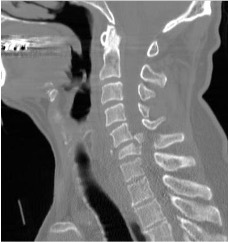

What is this ?

Cervical CT:

C6 compression # with post. fragment